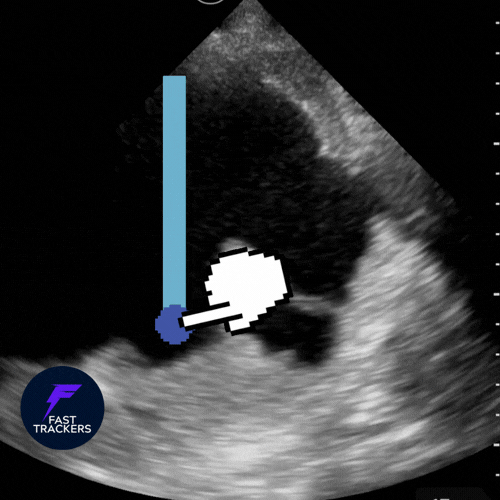

Quantification de l'epanchement – formule de Balik

Installer le patient en décubitus dorsal (ou demi-assis si possible à 15°).

Utiliser une sonde convexe.

Se placer en ligne axillaire postérieure, coupe longitudinale.

Identifier l’épanchement (zone anéchogène entre poumon et paroi).

Mesurer la distance maximale entre la plèvre pariétale et la plèvre viscérale (en mm ou cm), en expiration.

Règle pratique

- Volume (mL) ≈ distance interpleurale (mm) × 20 (ou distance en cm × 200)

Repères cliniques utiles

< 10 mm : petit épanchement → surveillance le plus souvent.

10–20 mm : modéré → discuter ponction selon symptômes.

> 20–25 mm : significatif → ponction/drainage à envisager si dyspnée ou infection suspectée.

distance maximale entre la plèvre pariétale et la plèvre viscérale.